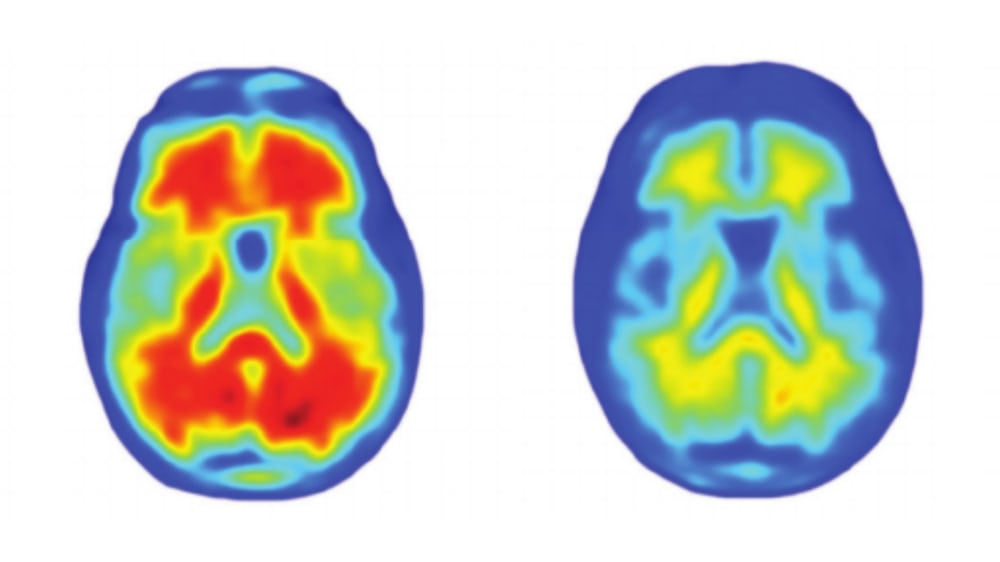

Команда ученых протестировала многообещающее лекарство от Альцгеймера, которое уже называют главным успехом в борьбе с заболеванием за последние 25 лет. Об этом сообщается на сайте The Telegraph. Ученые выяснили, что новый препарат эффективно борется с бета-амилоидами, которые провоцируют болезнь Альцгеймера. В ходе 6-месячного исследования первой группе добровольцев с начальной стадией болезни Альцгеймера делали настоящие инъекции, второй - плацебо. Спустя полгода у пациентов из первой группы бета-амилоидных бляшек в мозге стало значительно меньше. "Результаты клинического испытания внушают оптимизм: возможно, мы сделаем шаг вперед в борьбе с Альцгеймером", - комментируют авторы исследования. По словам ученых, разработанное лекарство как минимум сможет восстановить когнитивные способности пациентов с начальной стадией Альцгеймера и спасти их от деменции.